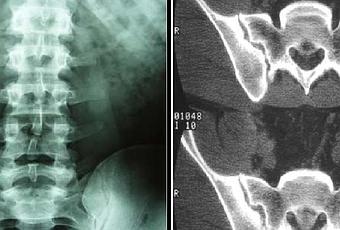

pelvianos o lumbares). El diagnóstico clínico se confirma por interrogatorio, y

palpación extra e intrarrectal. La coxigodinia se hace más evidente en la

posición sentada. RX una placa simple y otra placa sentado. El